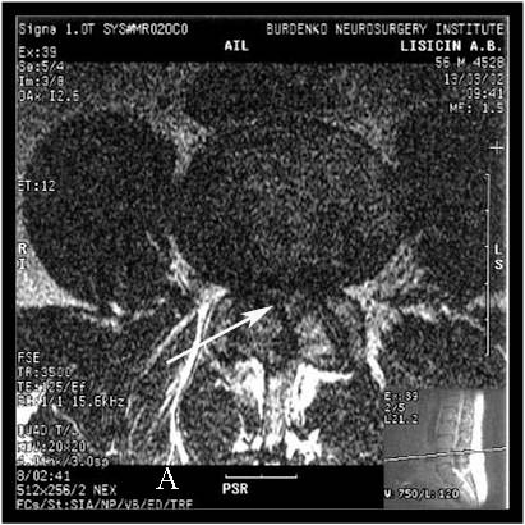

Стенозом позвоночного канала называют уменьшение его размера в передне-заднем направлении, а также уменьшение его ширины. Сужение позвоночного канала в поясничном отделе наиболее часто встречается при гипертрофии (увеличении) фасеточных суставов, желтой связки, уменьшении фораминального отверстия (места выхода нервного корешка из позвоночного канала) за счет разрастания остеофитов, изменении оси позвоночника (сколиоз, спондилолистез). (Рис.1,2А,В)